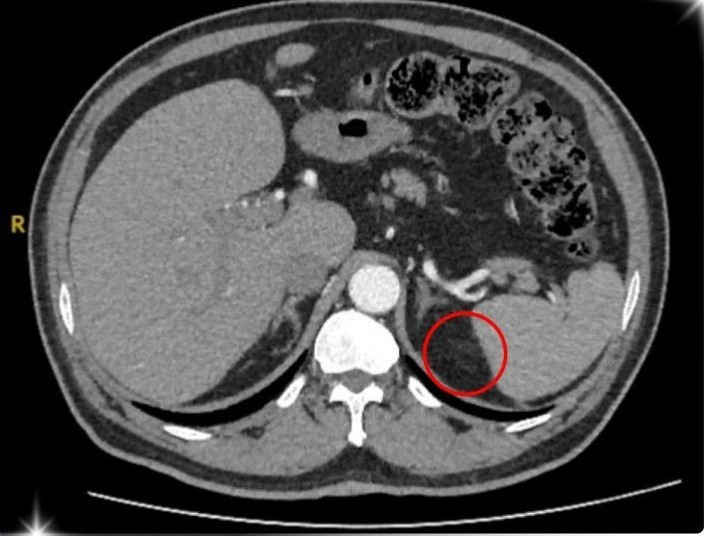

U tuyến thượng thận trên phim chụp - Ảnh BVCC

Sau quá trình kiểm tra kỹ lưỡng và chụp hình ảnh MSCT 160 lát vùng ổ bụng của bệnh nhân u tuyến thượng thận, ông T. được xác định mắc phải hội chứng Conn (hay còn gọi là cường Aldosterone tiên phát) – một bệnh lý hiếm gặp do khối u nhỏ ở vỏ tuyến thượng thận gây ra.